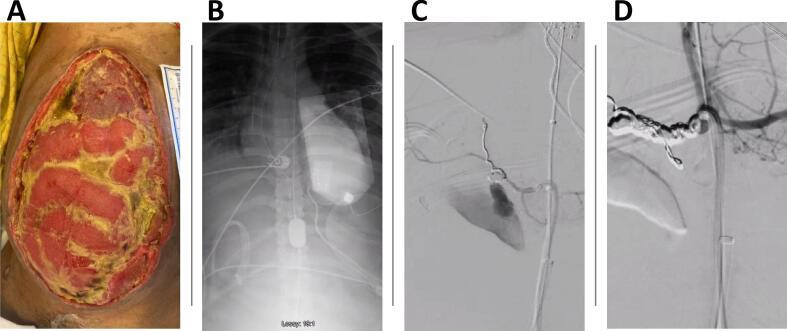

Hemorrhage is among the leading causes of death for trauma patients. Adjunct techniques used to control bleeding include use of aortic cross clamping, application of a pelvic binder, rapidly expanding hemostatic sponges, and extra-peritoneal packing. Additionally, Resuscitative Endovascular Balloon Occlusion of the Aorta (REBOA) can provide life-saving proximal control for patients with massive internal hemorrhage. This study concerns a patient treated with Zone 1 REBOA for class IV hemorrhagic shock from a spontaneous common hepatic artery rupture. REBOA was performed at bedside in the Surgical Intensive Care Unit (SICU) prior to definitive selective embolization. A healthy 28-year-old male suffered a grade 4 liver laceration and pancreatic head transection with associated duodenal injury after a high-speed motor vehicle collision. On arrival, the patient required a damage control laparotomy with multiple reoperations for management of his intra-abdominal injuries. By hospital day 11, significant visceral adhesions resulted in a frozen abdomen. On hospital day 20, the patient developed massive hematemesis, hematochezia, and class IV hemorrhagic shock. Vascular surgery was called to bedside in the SICU to perform REBOA. The patient received massive transfusion protocol while a 12 Fr sheath was inserted, and an aortic occlusion balloon was inflated in Zone 1 allowing for hemodynamic stabilization for transport and definitive management in the angiography suite. This case reports a novel use of REBOA, at bedside in the SICU, for the management of a massive gastrointestinal bleed in a patient with frozen abdomen. In this case, REBOA allowed us to achieve temporary hemodynamic stability prior to definitive control in the angiography suite. Bedside use of REBOA in the SICU prevented certain exsanguination and death.

出血是创伤患者的主要死因之一。用于控制出血的辅助技术包括使用主动脉交叉钳夹、应用骨盆固定带、快速膨胀止血海绵和腹膜外填塞。此外,复苏性血管内主动脉球囊阻断术(REBOA)可为大量内出血患者提供挽救生命的近端控制。本研究涉及一名因自发性肝总动脉破裂导致IV级失血性休克而接受1区REBOA治疗的患者。在进行确定性选择性栓塞之前,在外科重症监护病房(SICU)床边进行了REBOA。一名28岁健康男性在高速机动车碰撞后发生4级肝裂伤、胰头横断伤并伴有十二指肠损伤。入院时,患者需要进行损伤控制剖腹术并多次再次手术以处理其腹腔内损伤。到住院第11天,严重的内脏粘连导致腹部冻结。在住院第20天,患者出现大量呕血、便血和IV级失血性休克。血管外科医生被召至SICU床边进行REBOA。在插入12F鞘管时,患者接受了大量输血方案,并且在1区充盈了主动脉阻断球囊,从而实现了血流动力学稳定,以便转运至血管造影室进行确定性治疗。本病例报告了在SICU床边使用REBOA治疗腹部冻结患者大量胃肠道出血的新方法。在本病例中,REBOA使我们能够在血管造影室进行确定性控制之前实现暂时的血流动力学稳定。在SICU床边使用REBOA避免了某些失血和死亡。